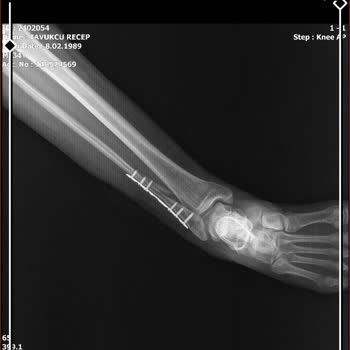

Adana Medical Park Hastanesinde Dr. C*** Özkan ayak ameliyatımı yaptı ve ayağım eskisinden çok daha kötü oldu. Ameliyat esnasında ayaktaki dokulara zarar verdiği için ayağımda his kaybı oluştu. 2 yıl geçmesine rağmen ayağa kalkmakta ve yürümekte çok zorlanıyorum. Bu doktor da hastane yönetimi de mad...